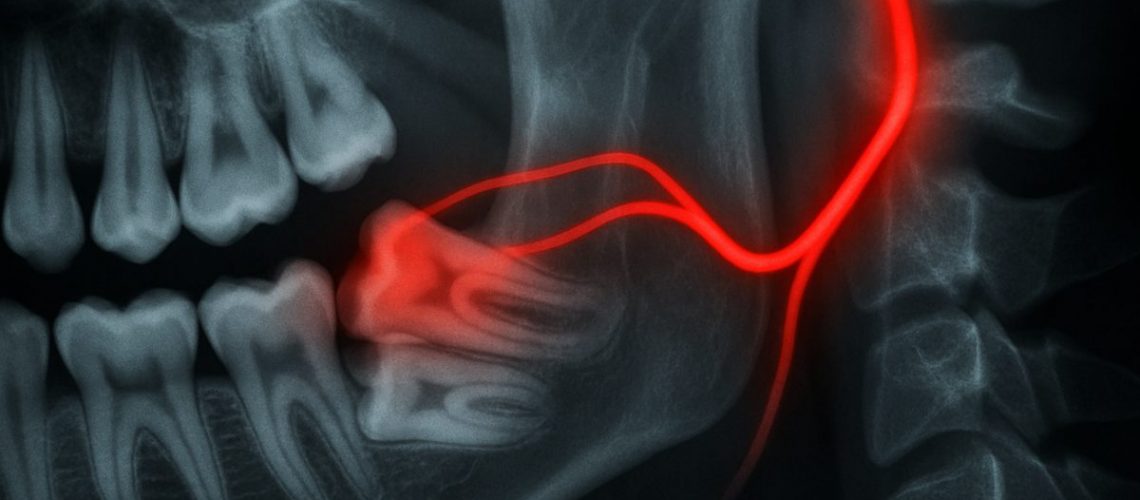

Imaging And Tests (X-Ray, CBCT) To Find The Source

Dental X-rays or a CBCT scan can reveal impacted wisdom teeth, infections, or bone involvement. Imaging helps pinpoint whether the pain source is a tooth, a jaw joint problem, or an ear-related issue. For suspected infections, your clinician may check for swelling, pus, or lymph node enlargement.